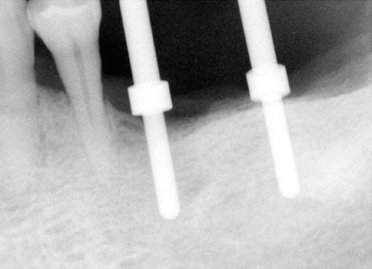

Fig.4 (left) and 5 (right) Model surgery was performed to insert guiding rods for #19 and 20 (Fig.4). At that time, it was thought that the implant #19 is more likely to invade the mental nerve loop. It bends upward and distally. Effort was made to design #19 osteotomy as distally as possible, as shown by the metal tube inside acrylic in Fig.5. The tube exits at the distal fossa of waxed-up tooth #19. Retrospectively, the angulation for #20 is not correct (Fig.4). The axis for #20 in Fig. 5 is more appropriate. A guiding tube was inserted over a rod at #20. The rod and tube are purchased from Straumann. |